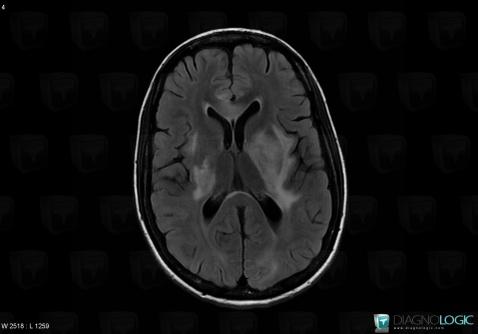

Toxoplasmosis, Basal ganglia and capsule, MRI

Here is the specific information in the key image above:

- Diagnosis Toxoplasmosis (link to Abscess), Location(s) Basal ganglia and capsule, with gamuts Basal ganglia T2W or FLAIR hyperintense lesion